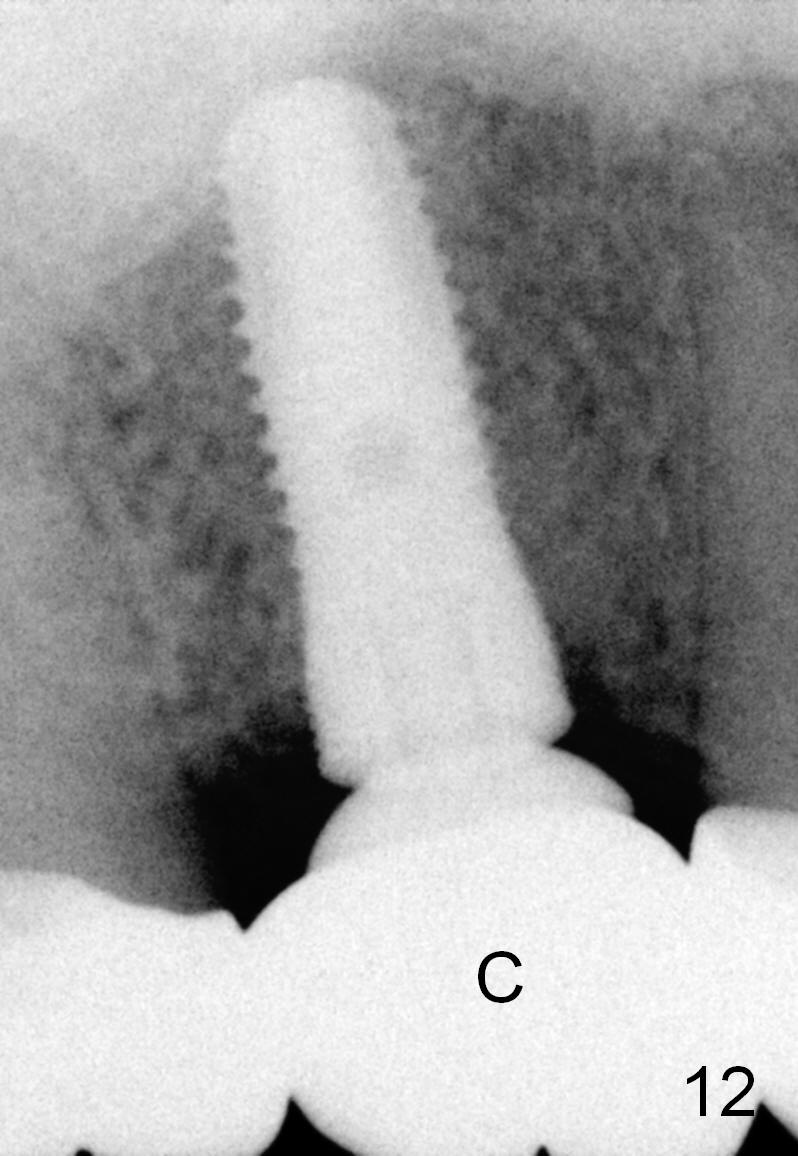

The bone density (Fig.1 white *) at the edentulous area (#3) is lower than that at the dentulous one (black *, 50 year-old man). The buccal plate is also atrophic and concave (Fig.2,3 arrowheads). A series of bone expanders are used to form osteotomy (following 1.6 mm pilot drill) at the depth of 14 mm (Fig.3 E 3.0 mm in diameter). When the last expander (4.3 mm) is removed from the osteotomy, the buccal plate appears to have been moved buccally (Fig.5 arrowheads). A 5.3x14 mm submerged implant (Fig.6 I) is placed with insertion torque >35 Ncm. The buccal plate seems to improve following placement of an 8.2 mm healing abutment and suturing (Fig.7). No bone graft is used. The buccal plate remains normal 12 days postop (Fig.8). It is slightly concave 3 months postop (Fig.9) with minimal bone resorption at the crest (Fig.10 (H: healing abutment),11 (A: cemented abutment). Nine months post cementation (12 months postop), bone resorption at the crest remains minimal (Fig.12) while the buccal plate (Fig.13 *) at #3 remains strong. Bone loss appears not to get worse 22 months post cementation (Fig.14). Soft and hard tissues remain healthy around the implant crown 3 years (Fig.15) and 3.5 years (Fig.16,17) post cementation.